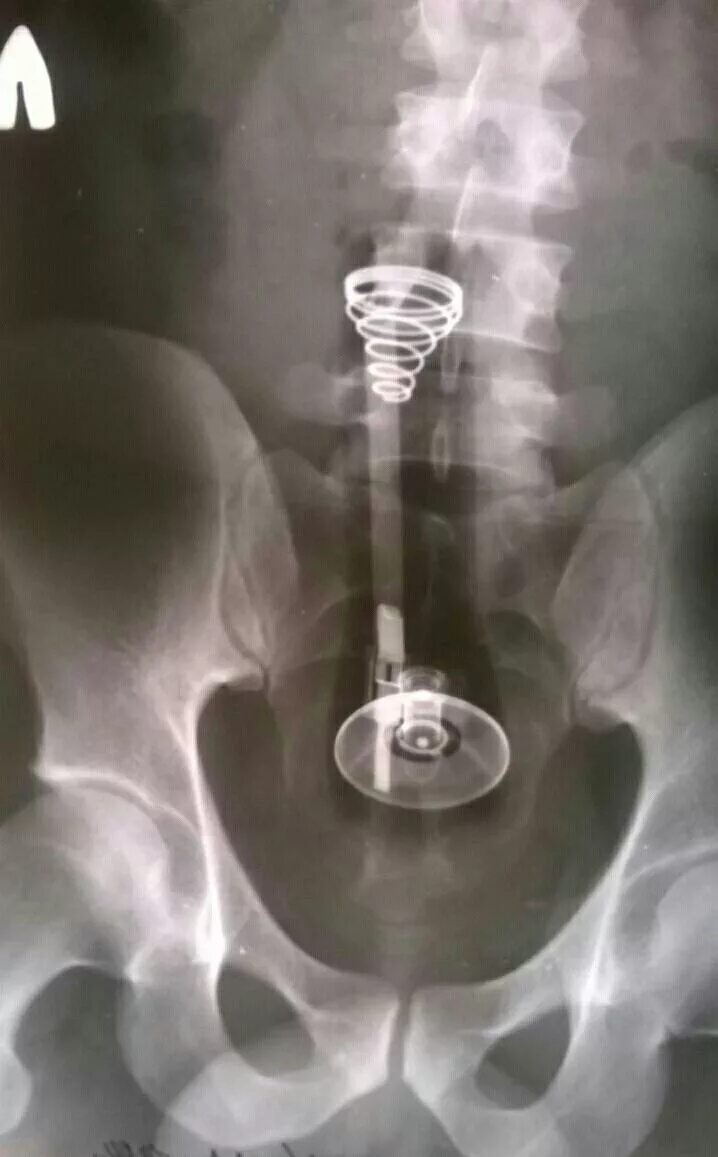

Длинные предметы в девушках